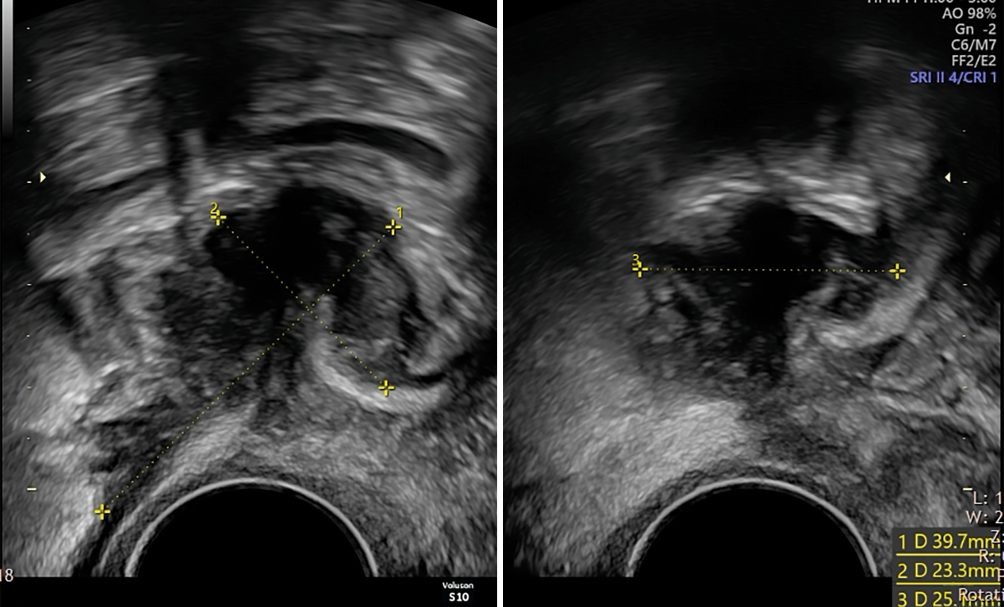

Abb. 5

Die WSL (weisse Pfeile) ist an der Uterushinterwand unterbrochen und unscharf begrenzt (Pfeilspitzen). Ursache ist eine adhärente Endometrioseläsion (Sternchen)

Bild vergrößern

Nachgewiesene Läsionen sollten in zwei Ebenen mit drei Massen erfasst werden (Abb. 6).

Abb. 6

Tiefe Endometriose des Rektums mit einer maximalen Ausdehnung von 39,7 mm (#Enzian C3)